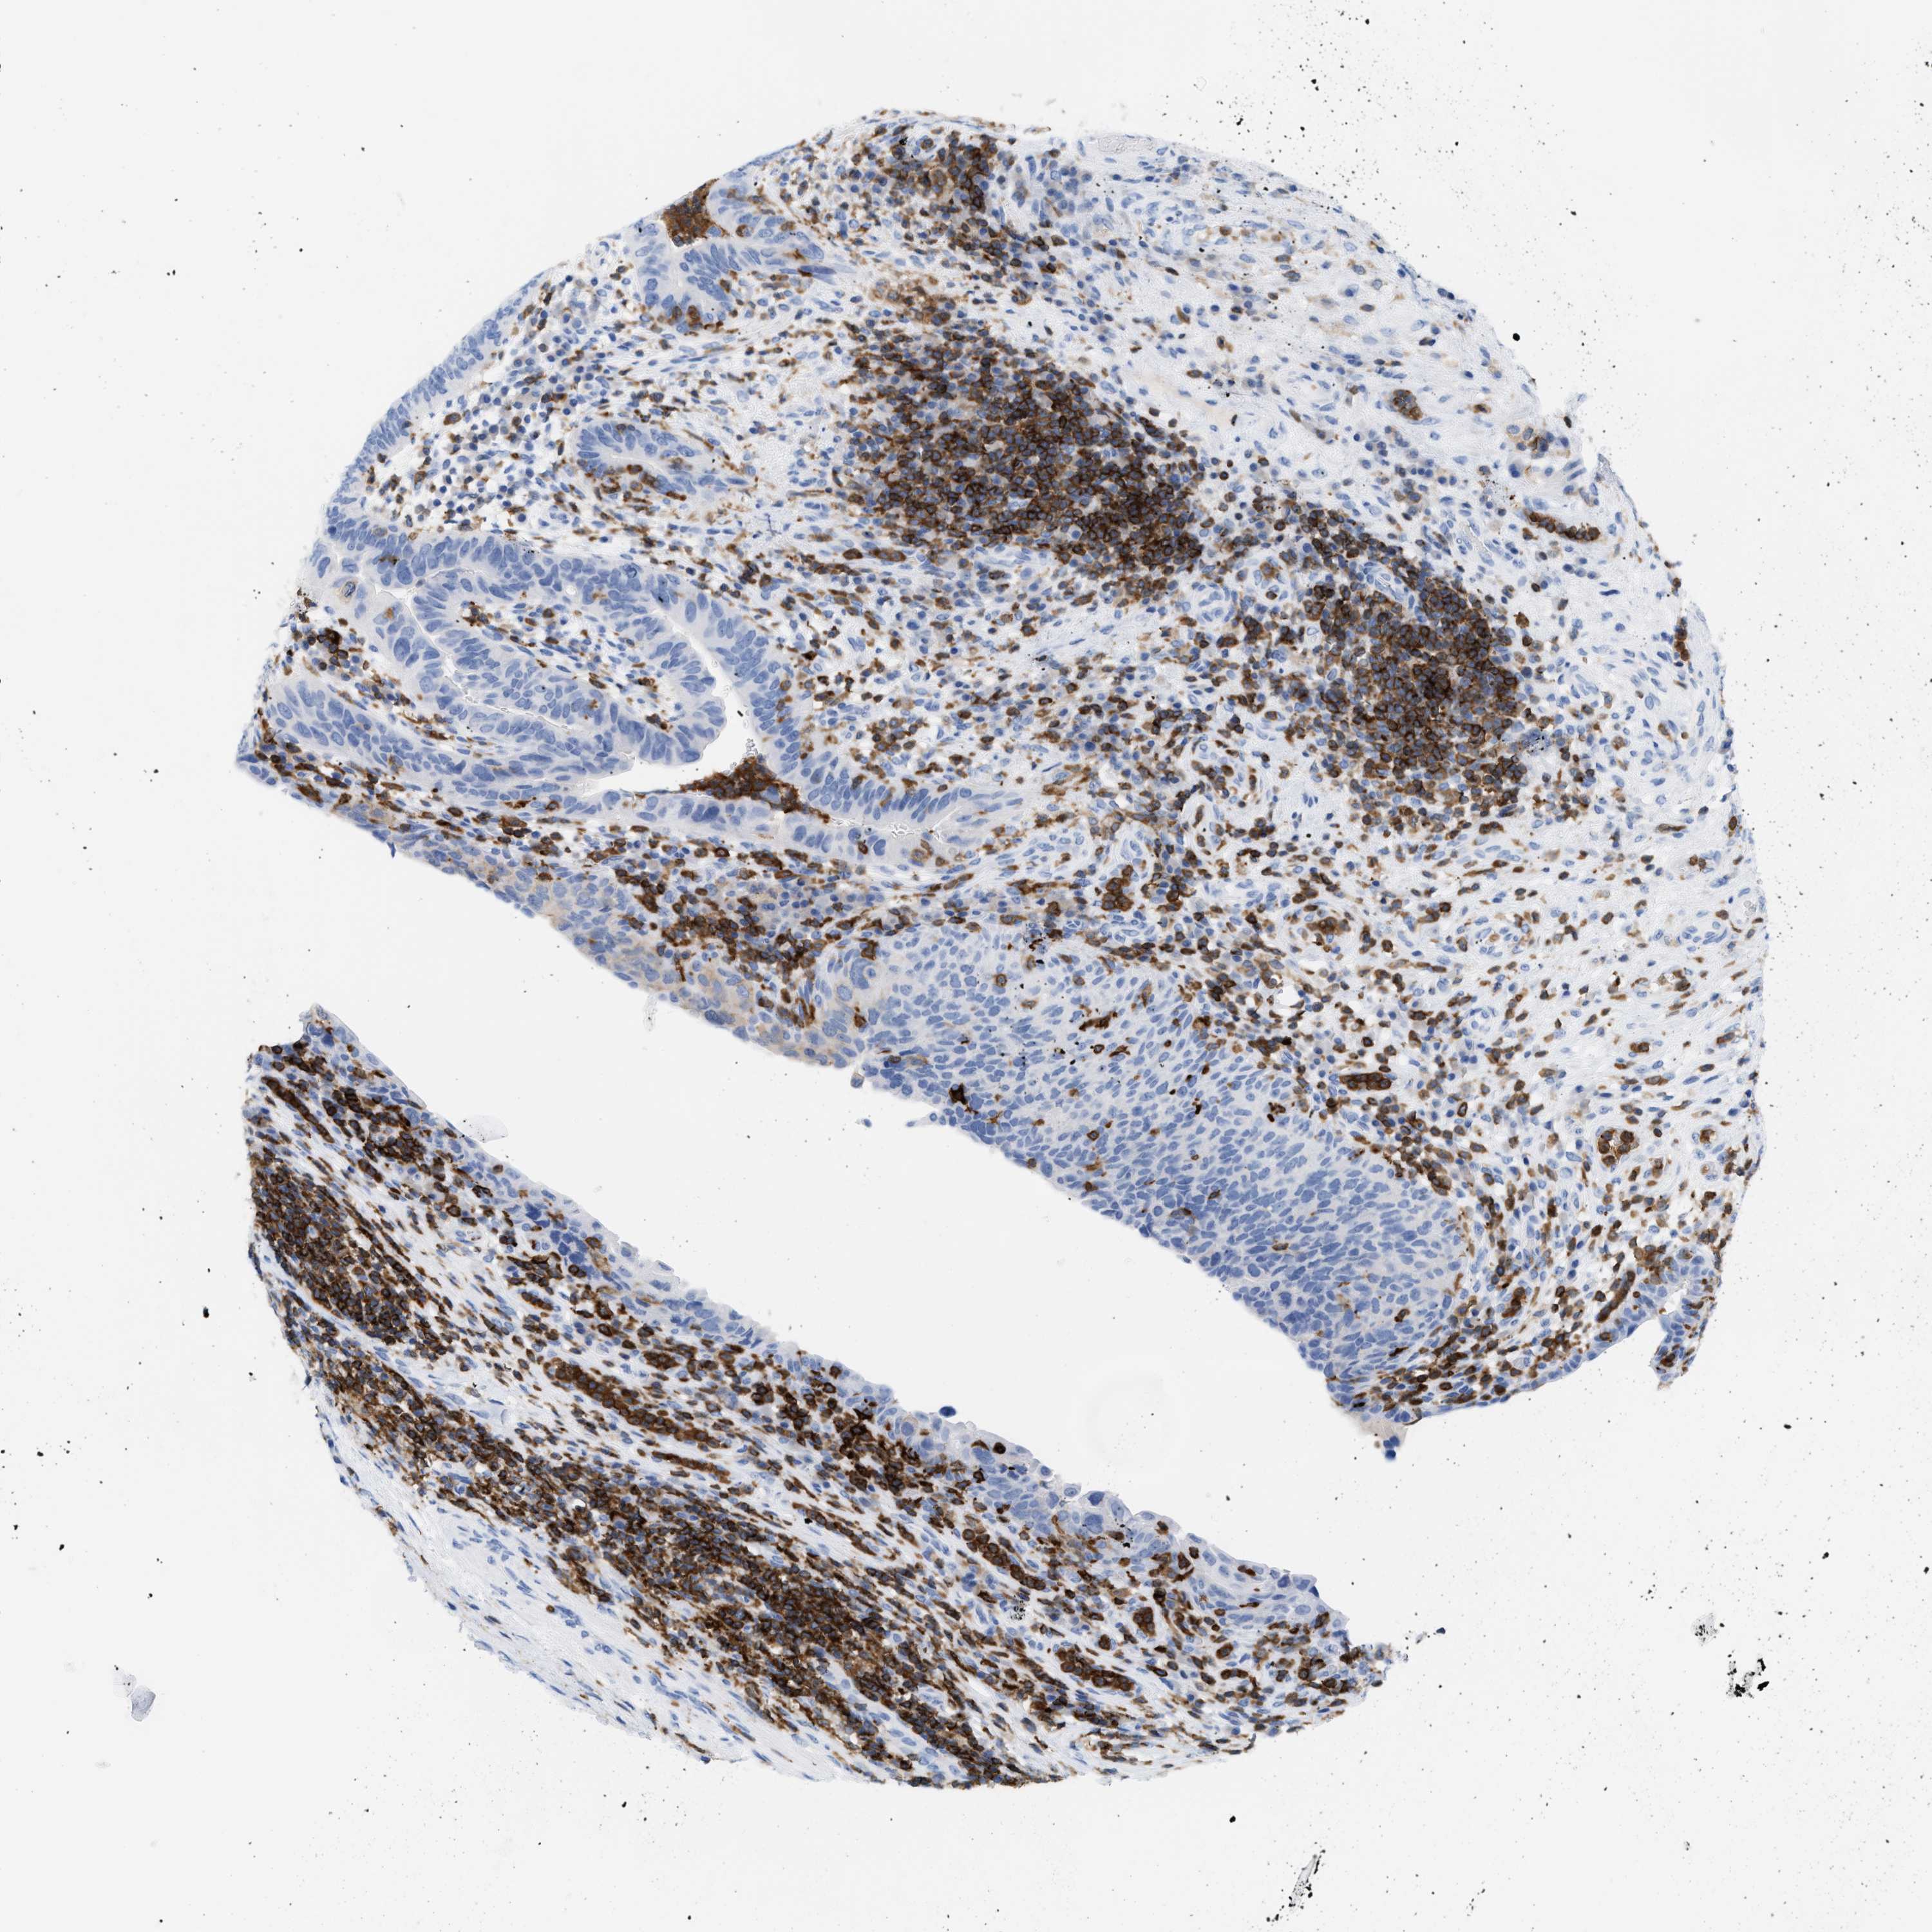

UROTHELIAL CANCER - Protein expressioni

A mouse-over function shows sample information and annotation data. Click on an image to view it in a full screen mode. Samples can be filtered based on level of antibody staining by selecting one or several of the following categories: high, medium, low and not detected. The assay and annotation is described here.

Antibody stainingi

Antibody staining in the annotated cell types in the current human tissue is reported as not detected, low, medium, or high, based on conventional immunohistochemistry profiling in selected tissues. This score is based on the combination of the staining intensity and fraction of stained cells.

Each image is clickable and will lead to virtual microscopy that enables deeper exploration of all samples and also displays staining intensity scores, fraction scores and subcellular localization as well as patient and tissue information for each sample.

Antibody CAB020673

Urothelial carcinoma, Low grade

Urothelial carcinoma, High grade